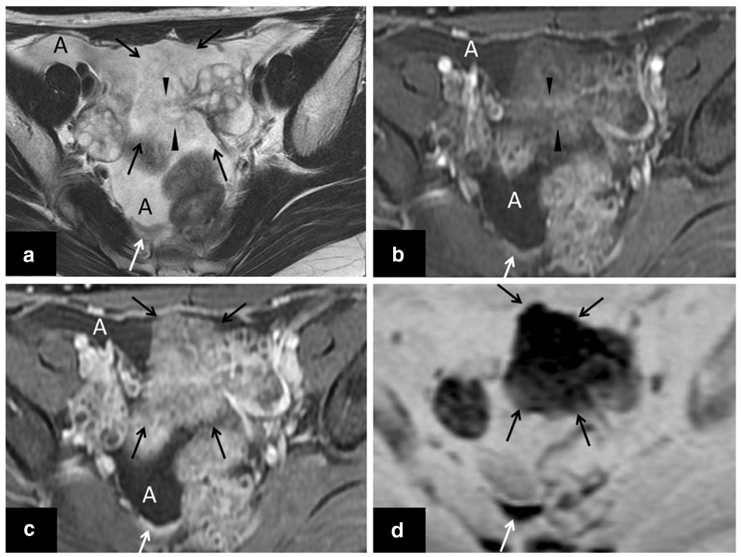

【外向性発育を示すSBT ②】

• MRI所見

【外向性発育を示すSBT ①】

Sahin H, et al. Br J Radiol. 2021;94:20210116.

Tsuboyama T, et al. RadioGraphics. 2022;42:2095–2111

【外向性発育を示すSBT ③】